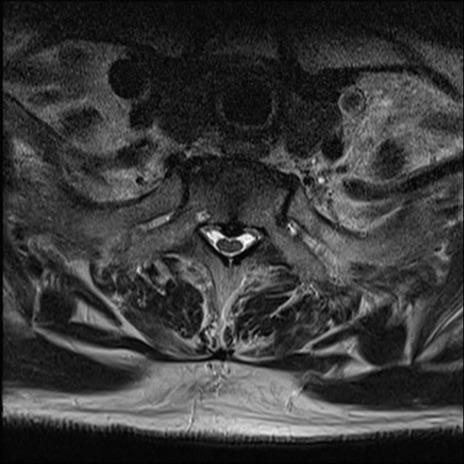

【整形】TIPS症例7 頚椎MRI T2WI(横断像)

頚椎MRI

矢状断像と横断像